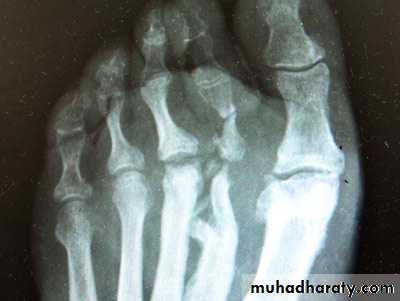

There is an erosive arthreopathy with predominant involvement of the terminal interphalangeal joints.Gout :

In gout ,the deposition of the urate crystals in the joint & in the adjacent bone gives arise to an arthritis which most commonly affects the metatarsophalangeal joint of the big toe .Radiological changes involving :

1.soft tissue swelling 2 . erosions 3 . usually no osteoporosis .4 . Tophi.